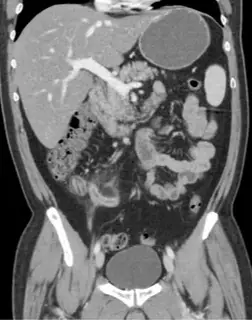

МРТ брюшной полости и забрюшинного пространства

Оценка состояния печени, желчного пузыря, поджелудочной железы, почек, надпочечников, лимфоузлов.